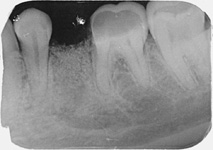

Nejlepším materiálem pro augmentace je vlastní kost pacient, kterou můžeme získat

např. odběrem z dolní čelisti pacienta. Jedná se o velmi šetrný, nenáročný výkon, který pacienta nijak nezatíží.